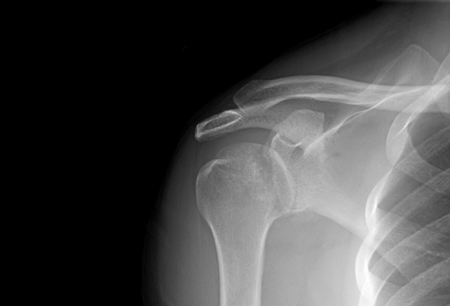

Joint dislocation

Anteroposterior x-ray view of a shoulder showing an anteroinferior dislocation

Personal collection of Dr Paul Novakovich